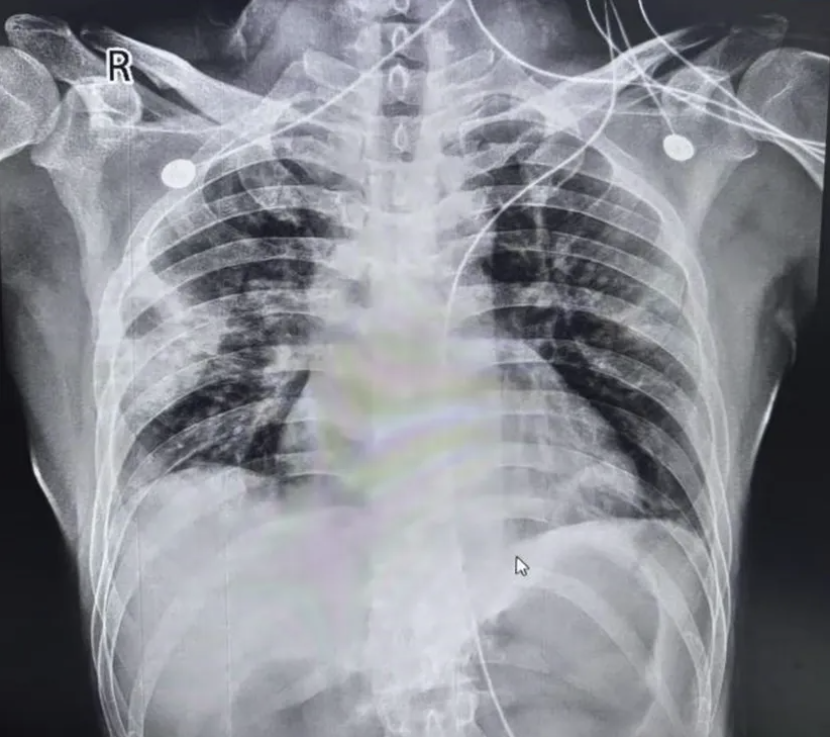

然而,复查时徐医生敏锐的发现:右下肺的磨玻璃影和渗出影非但没有减少,反而有局部增多趋势(图3)。但考虑这可能只是感染后的“延迟吸收”,加之患者自我感觉良好,便嘱咐其继续完成抗感染疗程。

图3. 复查胸片

然而,就在下一次复查前夕,病情急转直下。患者突发严重呼吸困难,在给予面罩高流量吸氧后血氧饱和度仍持续低于90%、缺氧症状未见缓解。

将患者转入ICU,并进行气管插管、连接有创呼吸机等急救措施。但即使给予高浓度氧通气,患者氧合指数依然低于150,表现为重度急性呼吸窘迫综合征(ARDS)样表现。为患者开具CT检查,结果显示:双肺出现广泛ILD表现,包括大片磨玻璃影、沿支气管血管束走行的网格影及实变影(图4)。疾病进展速度之快,令团队高度警惕。